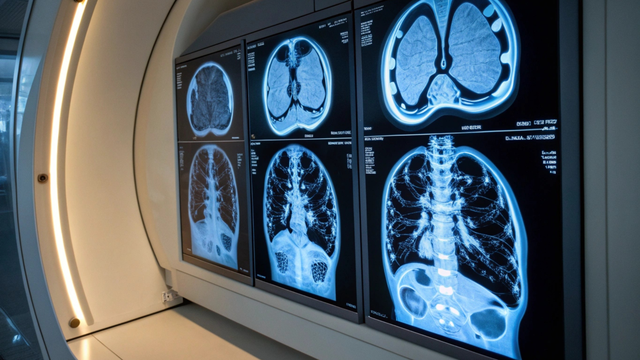

Tổng hợp các bài viết sức khỏe chủ đề chụp ct